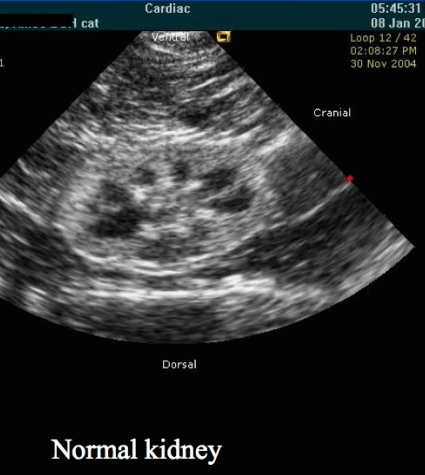

We did proceed with an abdominal ultrasound for Caramel.  For your reference, this is the appearance of a normal kidney on ultrasound:

Here are the images of Caramel's kidneys as viewed on abdominal ultrasound:

Abdominal ultrasound confirmed that Caramel has Polycystic Kidney Disease (PKD).

Kidney disease is a common health concern in cats and ultrasonography is a useful tool for investigation and diagnosis of kidney disease. As a diagnostic imaging modality, ultrasound can offer important anatomical information such as kidney size, shape, and internal architecture. A change in kidney size, shape, and contour can be an indication of kidney disease. One area where changes in kidney size can be helpful is in the differentiation of acute kidney injury from chronic kidney disease. Increased size is more commonly seen with acute injury, whereas reduced kidney size suggests chronic disease.